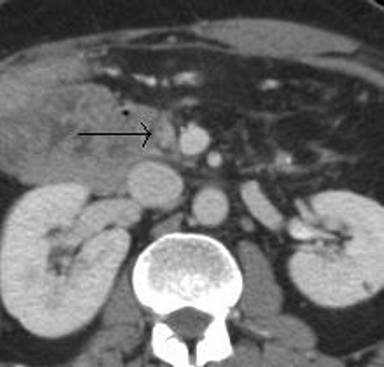

Pancreas-preserving total duodenectomy was performed in 2009, with fashioning of a neoduodenum from jejunum. Histopathological examination of the resected specimen revealed a focus of adenocarcinoma. Post-operative baseline computerised tomography (CT) revealed no peripancreatic abnormality (Figure 1). Follow-up CT after one year demonstrated a 2 cm hypodense mass between the neoduodenum and the uncinate process (Figure 2), although he remained clinically well. Following further discussion at the multidisciplinary team meeting, it was decided that EUS-guided biopsy (EUS-FNA) should be performed.

Figure 1. Post-operative baseline axial CT demonstrating part of the uncinate process (black arrow) adjacent to the collapsed neoduodenum. |